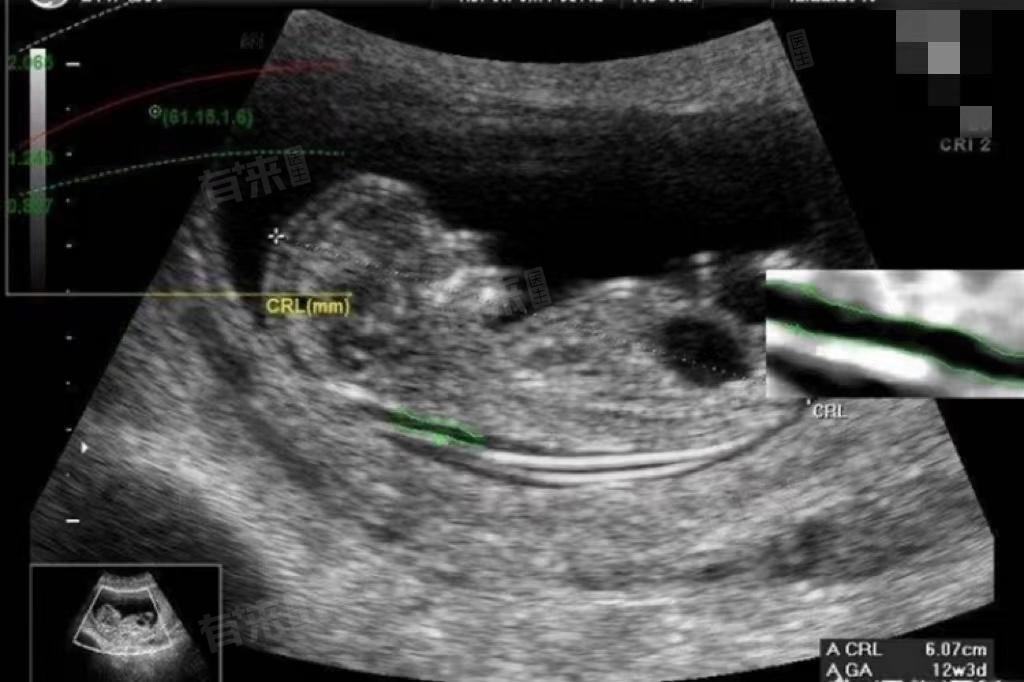

1、确定检查时间:NT检查的时间是孕11-13周+6天,此时胎儿的颈项透明层厚度相对稳定,测量结果较为准确。